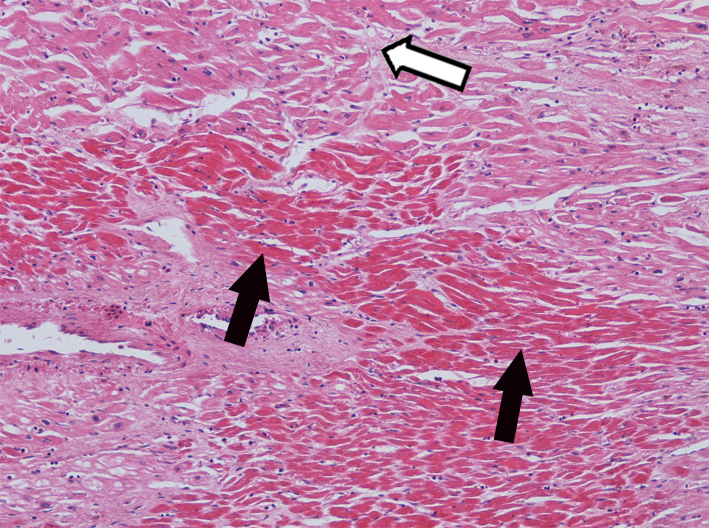

6.Myocardial infarction